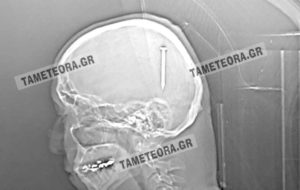

Σε επιτυχημένη επέμβαση αφαίρεσης καρφιού από το κρανίο υποβλήθηκε ένας κάτοικος της Καλαμπάκας. Συγκεκριμένα, κατά τη διάρκεια εργασιών σφηνώθηκε στο κεφάλι του ένα καρφί 5 εκατοστών, ευτυχώς όπως αποδείχθηκε σε σημείο που δεν μπορούσε να του προκαλέσει περαιτέρω προβλήματα.

Ο Καλαμπακιώτης αναρρώνει υπό παρακολούθηση στο νοσοκομείο, χωρίς η κατάσταση της υγείας του να εμπνέει ανησυχία.